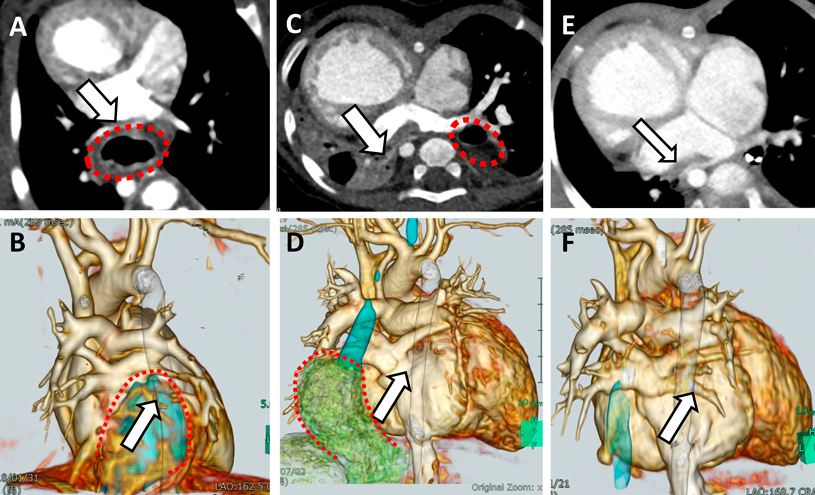

術後合併症として十二指腸狭窄合併が3例に認められた.症例5(Fig. 2)では,十二指腸狭窄解除術における術中所見で血管の走行異常があった.靭帯に覆われた肝動脈が十二指腸前面を走行しており(十二指腸前肝動脈),滑脱していた全胃を腹腔内に還納したことにより十二指腸が異常靭帯と十二指腸前肝動脈に圧排されて狭窄を来していた.また症例6では,滑脱した全胃を腹腔内に還納後,十二指腸前方に総胆管が走行することが判明した.開腹手術に移行し十二指腸バイパス術を追加することにより,総胆管による十二指腸狭窄を回避した.

Fig. 2 Post operative duodenal obstruction due to compression by abnormal ligaments and vessels (Case 5)

A: Preoperative schema of abdominal organs. B: Postoperative contrast study of upper gastrointestinal tract. The contrast medium is stuck in the stomach due to duodenal stenosis. C: Operation record of re-operation. Abnormal ligaments and vessels (arrow) obstruct the duodenum.